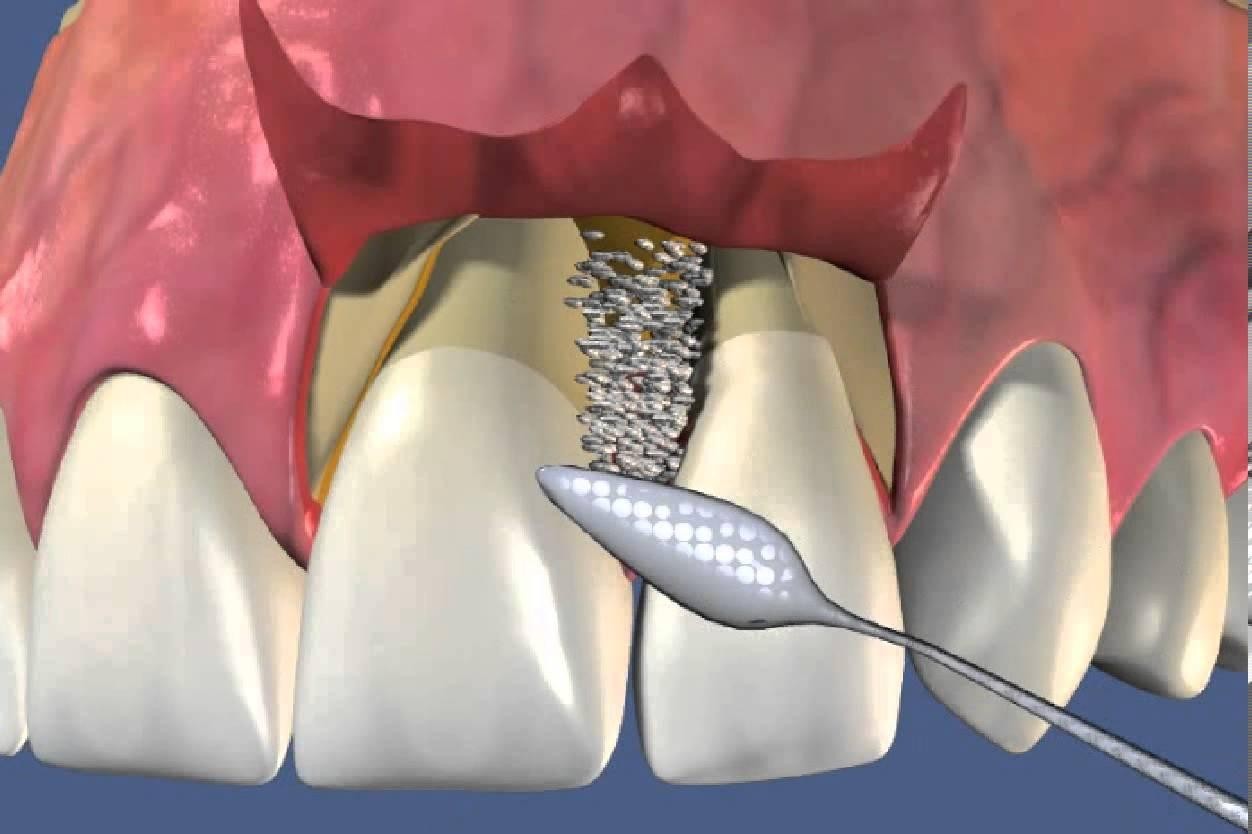

Фото и примеры имплантации зубов при пародонтите

Раздел: Необычные решения